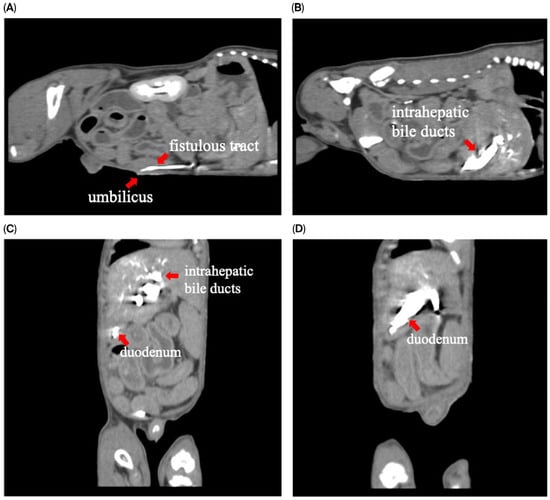

To assess for a persistent urachus, a positive contrast cystogram (KXO-80s, Toshiba, Tokyo, Japan) was performed using iohexal contrast medium (10 mL/kg, diluted to 100 mg I/mL; Omnipaque, GE HealthCare, Bangkok, Thailand). The cystogram demonstrated a contrast-filled structure extending from the apex of the urinary bladder as a convex outpouching of the lumen without evidence of contrast leakage toward the umbilicus (Figure 2). These findings were considered consistent with vesicourachal diverticula. An abdominal ultrasound examination was performed by using a real-time scanner (LOGIQ E9, GE, Fairfield, CT, USA) with a 13 MHz broadband linear transducer. Abdominal ultrasonography revealed a markedly dilated common bile duct (CBD; diameter 0.45 cm) and found an abnormal fistulous tract extending toward the umbilical region, while the gallbladder was not visualized (Figure 3). These findings raised the suspicion of an anomalous extrahepatic biliary tract or an ectopic remnant ductal structure. Therefore, an abdominal computed tomography (CT) scan (Optima 660, GE HealthCare, Bangkok, Thailand) with fistulogram was performed under general anesthesia (induction: propofol [8 mg/kg IV, Troypofol, Troikaa Pharmaceuticals Ltd., Gujarat, India], maintenance: 3% sevoflurane inhalation [Sevo, Singapore Pharmawealth Lifesciences Inc., Laguna, Philippines]). Iohexal contrast medium (2 mL/kg, 300 mg I/mL) was injected via a feeding tube inserted through the umbilicus. The fistulogram demonstrated a tubular tract filled with contrast medium extending from the umbilicus to the CBD and biliary tree, with passage of contrast into the duodenum (Figure 4). The CBD was dilated with contrast medium. In addition, CT imaging revealed the absence of the gallbladder, consistent with agenesis. Together, these findings were compatible with a congenital umbilicobiliary fistula with gall bladder agenesis. All the imaging techniques were performed and interpreted by a veterinary radiologist certified by the Thai Board of Veterinary Surgeons (sub-specialty of veterinary diagnostic imaging).

Figure 4. Computed tomography with fistulogram findings demonstrated contrast medium in (A) sagittal plane: the fistulous tract extending from the umbilicus; (B) sagittal plane: intrahepatic bile ducts; (C,D) coronal plane: intrahepatic bile ducts and duodenum.